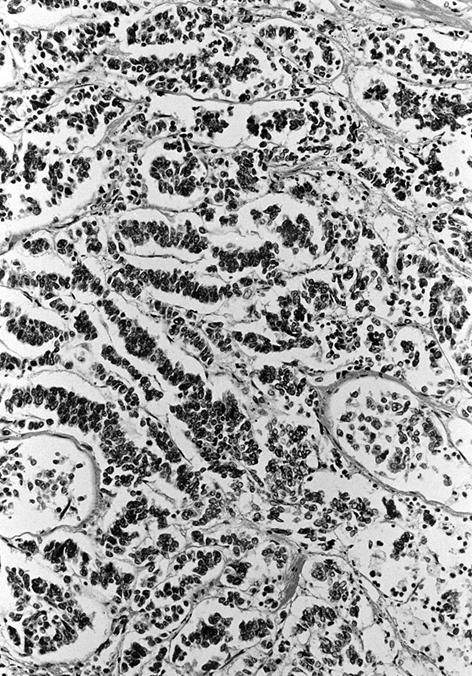

Microscopic (histologic) description

- Wide variety of morphology, can mimic any other thyroid malignancy

- Round, plasmacytoid, polygonal or spindle cells in nests, cords or follicles; often mixtures of these cells

- Round nuclei with finely stippled to coarsely clumped chromatin and indistinct nucleoli, occasional nuclear pseudoinclusion

- Eosinophilic to amphophilic granular cytoplasm due to secretory granules

- Generally low mitotic figures

- Stroma has amyloid deposits from calcitonin, prominent vascularity with glomeruloid configuration or long cords of vessels (Am J Surg Pathol 1995;19:642), coarse calcifications, occasional psammoma-like bodies

- Mucin in 42% (Arch Pathol Lab Med 1983;107:70)

- Often angiolymphatic invasion

- Occasionally marked neutrophilic infiltrate, oncocytic tumor cells, papillary patterns

- May entrap follicles

- C cell hyperplasia present in familial but not sporadic cases

Microscopic (histologic) images

Contributed by Shuanzeng Wei, M.D., Ph.D., Joseph Christopher Castillo, M.D. and Mark R. Wick, M.D.

AFIP images